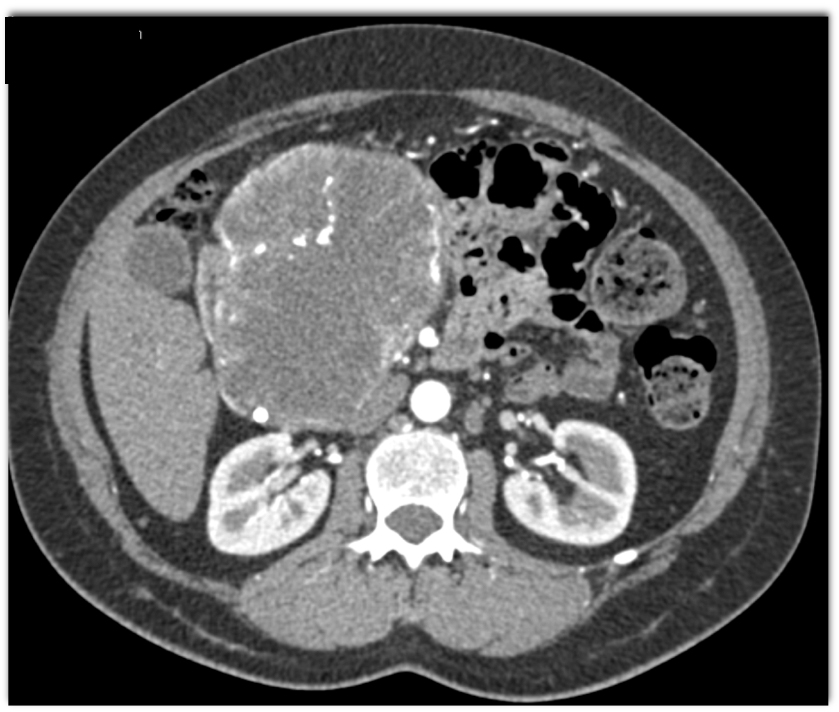

The most likely diagnosis in this 50ish year old woman is?

SPEN tumor

serous cystadenoma

neuroendocrine tumor

Mucinous Cystic Neoplasm (MCN)